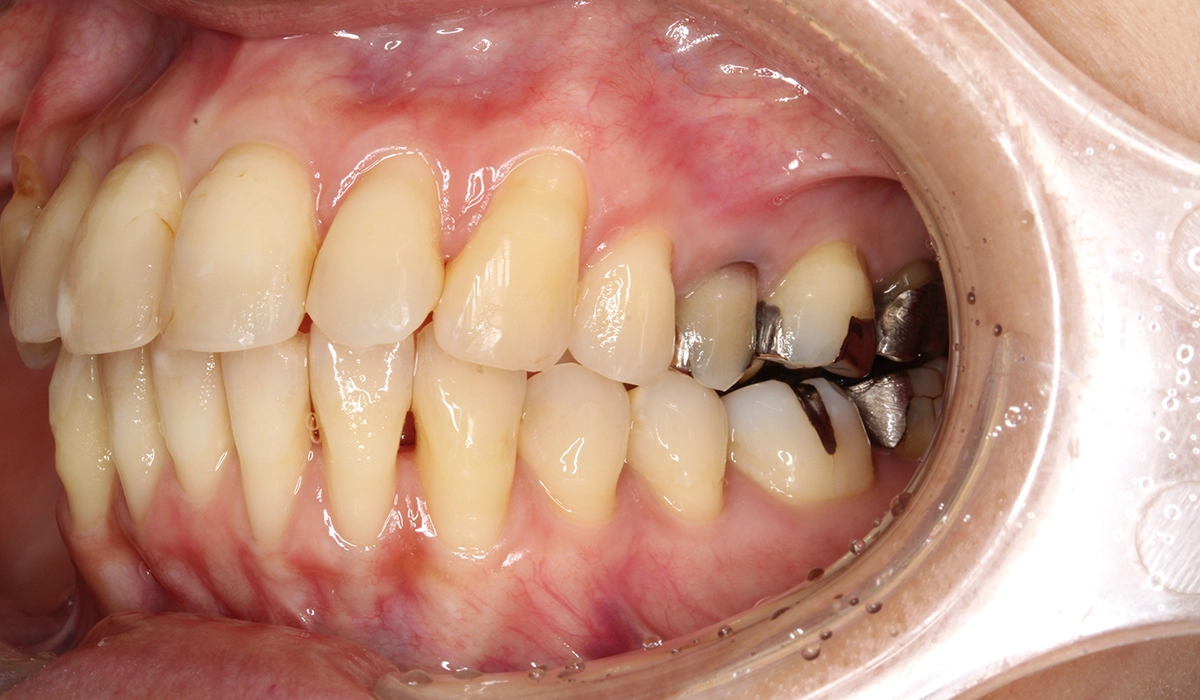

術前:左側

術後:左側